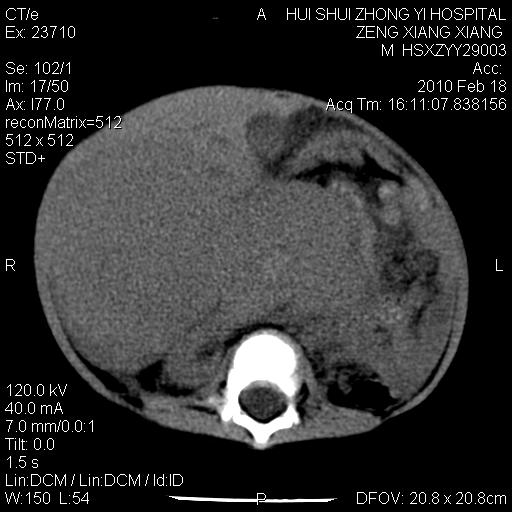

标题: PED3106:男,2岁,腹胀1月。 [打印本页]

标题: PED3106:男,2岁,腹胀1月。

定位腹膜后,肾上腺来源;

定性:恶性神经源性,肾上腺神经节母细胞瘤可能性大。

鉴别:肝母、肾母、肝脏中胚层错构瘤。

依据:年龄、有钙化,肾脏及肝脏受压移位。

肝母细胞瘤可能性大,右肾形态大体可见,不支持肾母细胞瘤,右肾移位不明显,肾上腺神经母细胞瘤可能性不大。